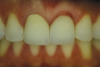

Fig 14. Follow-up 12 months after cementation.

Figure 14

Follow-up was assessed at 3, 6, 12 (Figure 14), 24, and 32 months (Figure 15 and Figure 16). Optimal integration of restorations and soft tissues was evidenced at the follow-up visits. The patient was very satisfied with the esthetics and function.